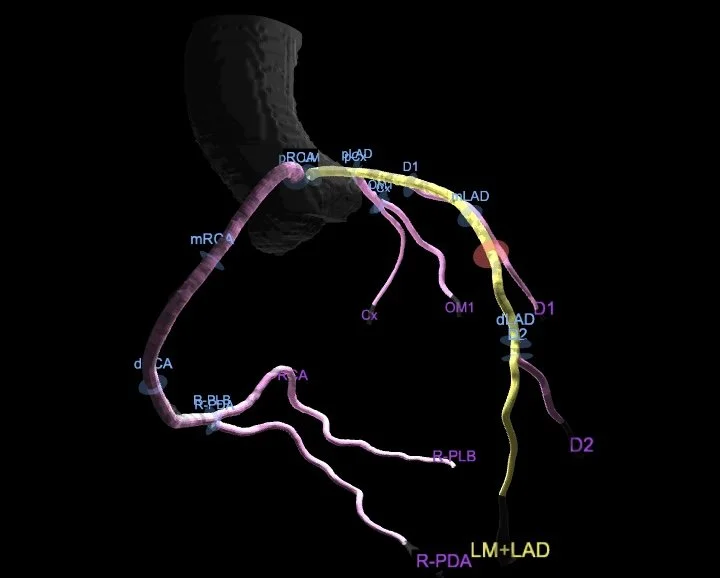

Coronary Computed Tomography Angiography (CCTA) is a noninvasive imaging study that, through the injection of contrast dye via an IV in your arm vein, identifies plaque, narrowing, or blockages in the coronary arteries. This advanced procedure employs a series of X-rays to produce detailed 3D images of your heart and coronary arteries, generating images previously only attainable through invasive heart catheterization.